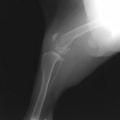

症例:右大腿骨遠位部の肉腫 クランバー・スパニエル 9歳 雌(未避妊)

2か月前から右後肢の完全挙上が認められ、消炎剤による内科治療で改善しないとのことで、他院から紹介来院した。

レントゲン検査

骨生検および病理組織検査

レントゲン検査所見から、骨もしくはその周囲組織に発生した腫瘍の可能性が考えられたため、病変部の細胞診検査およびジャムシディ生検針を用いた病変の骨生検を実施した。病理組織検査の結果、非上皮性の悪性腫瘍である“肉腫”と診断された。

内科治療に反応が乏しい四肢の跛行や疼痛は、本症例のように腫瘍が原因となっていることがあるため、レントゲン検査、骨生検等積極的に原因追及のための検査を実施することが必要である。骨の破壊を起こす悪性腫瘍は、非常に強い痛みを伴い、消炎鎮痛剤を用いても痛みを抑えることが困難となる。痛みの除去および腫瘍の治療のために断脚手術や抗がん剤等が必要となる場合があり、似た症状を示す整形外科疾患等とは治療法・予後が異なるため、その鑑別は重要である。